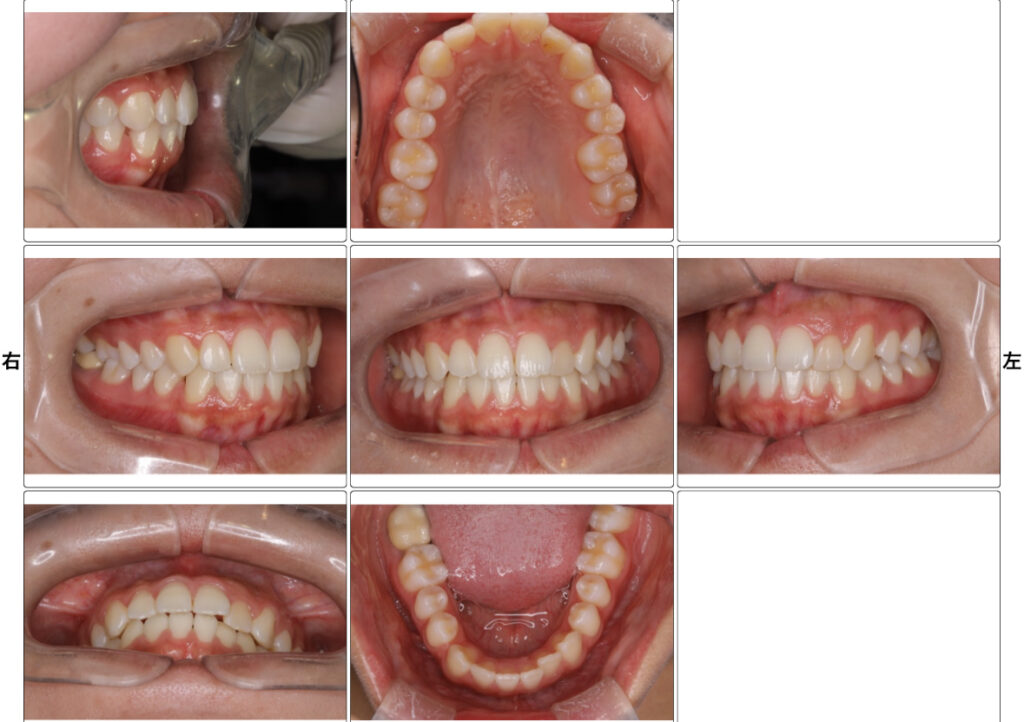

4.写真撮影📷

「口腔内写真(お口の中の写真)」「お顔の写真」を数枚撮影します。

治療前の状態を記録しておくことで、今後の治療計画や経過観察にも役立ちます。

お口周りにプラスチック製の器具をかけ、唇が写り込まないようにします。また、歯の裏側や噛み合わせを確認するために、温かい鏡を入れて撮っています。ここで温かい鏡を使用している理由は、患者様の息で曇らないようにするための工夫です!